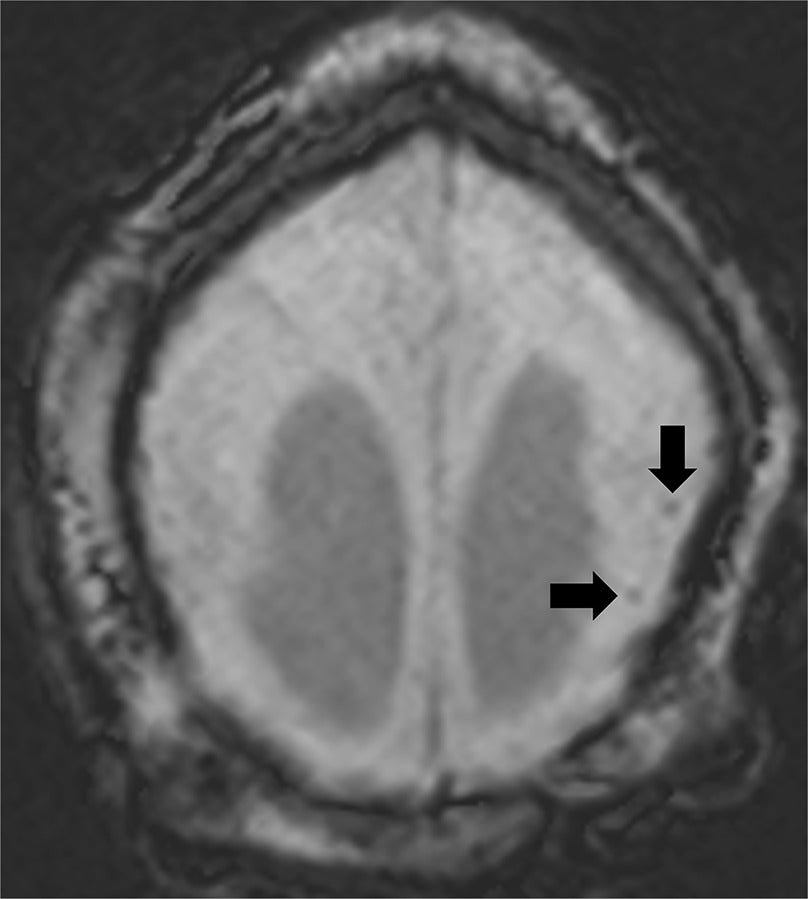

Axial susceptibility weighted imaging brain MRI demonstrating markedly diffuse simplified gyral pattern and scattered peripheral parenchymal calcifications.